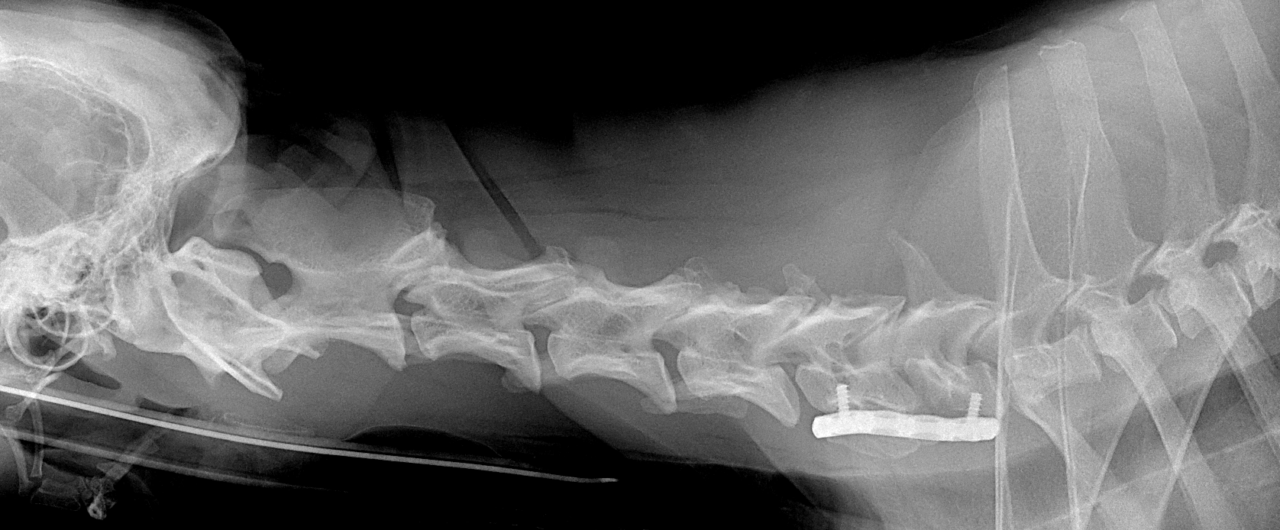

大型犬がふらつき、運動失調を主訴に来院しました。MRIで尾側頚椎C6~C7間の椎間板ヘルニアに続発した頚椎不安定症が疑われました。C6~C7をVentaral Slotで脊髄の除圧を行うと同時に、不安定性解消目的にC6〜C7を3.5Taitanium Locking Plateによるセメントレス固定術を行いました。しばらくは安静が必要です。